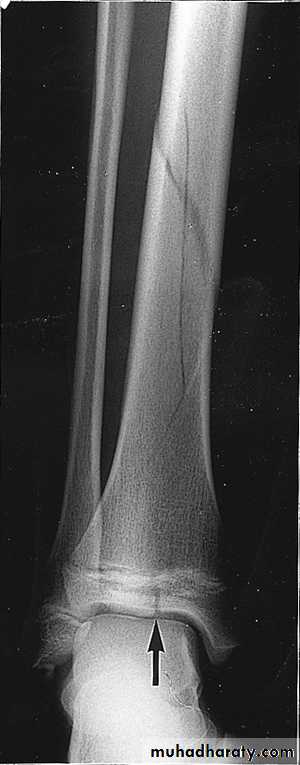

According to completeness

- incomplete

INCOMPLETE FRACTURE